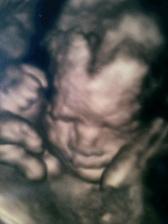

17.7.2010 dnesj jsme byli na 4D ultrazvuku..nádherný zážitek, Obě miminka se ukázala, jen Samík dělal chvilku drahoty. Jsme neuvěřitelně podobný rodičům..podle fotek z dětství je Samík celej tatínek a Vanesska celá já 🙂